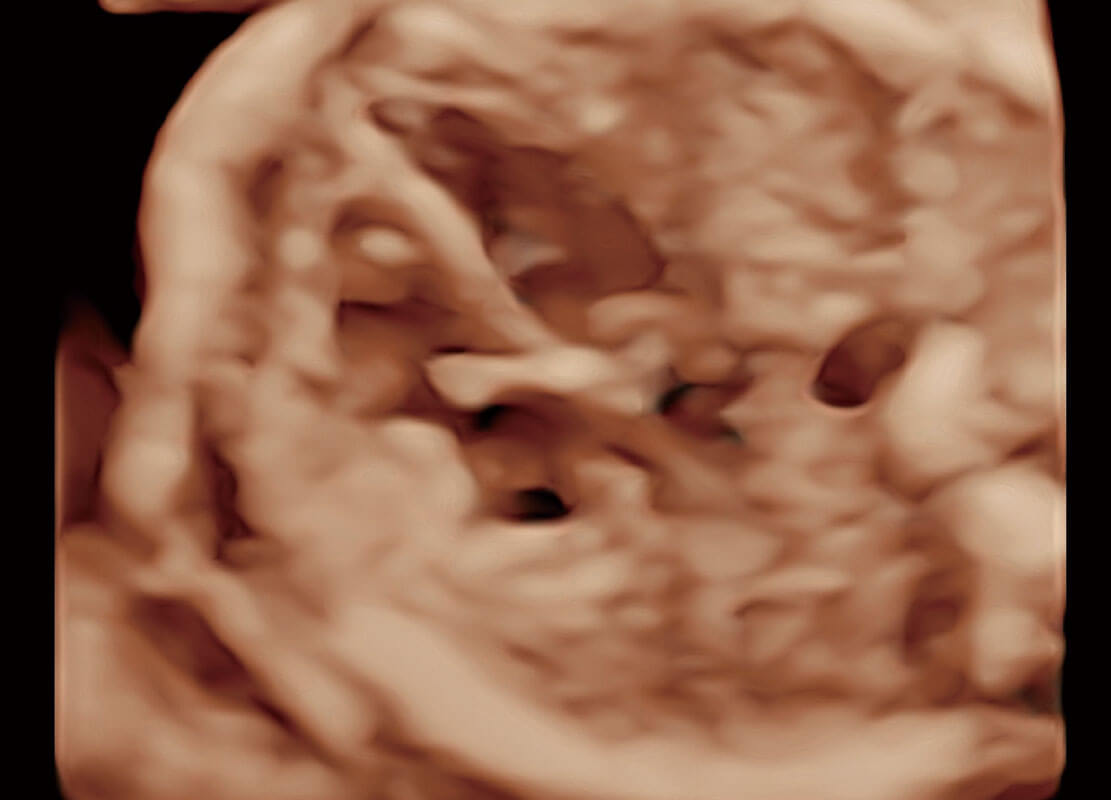

• 高分辨率容积成像-早孕胎儿

• 光影成像-孕囊